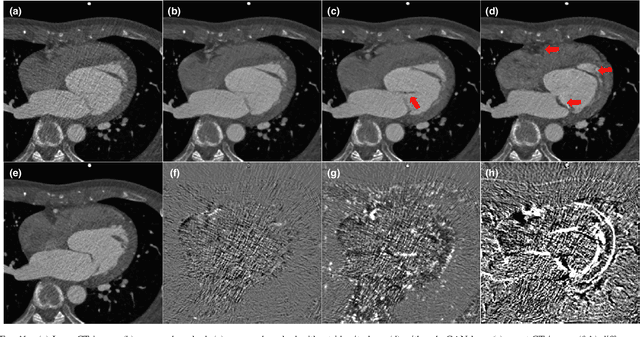

Abstract:In coronary CT angiography, a series of CT images are taken at different levels of radiation dose during the examination. Although this reduces the total radiation dose, the image quality during the low-dose phases is significantly degraded. To address this problem, here we propose a novel semi-supervised learning technique that can remove the noises of the CT images obtained in the low-dose phases by learning from the CT images in the routine dose phases. Although a supervised learning approach is not possible due to the differences in the underlying heart structure in two phases, the images in the two phases are closely related so that we propose a cycle-consistent adversarial denoising network to learn the non-degenerate mapping between the low and high dose cardiac phases. Experimental results showed that the proposed method effectively reduces the noise in the low-dose CT image while the preserving detailed texture and edge information. Moreover, thanks to the cyclic consistency and identity loss, the proposed network does not create any artificial features that are not present in the input images. Visual grading and quality evaluation also confirm that the proposed method provides significant improvement in diagnostic quality.